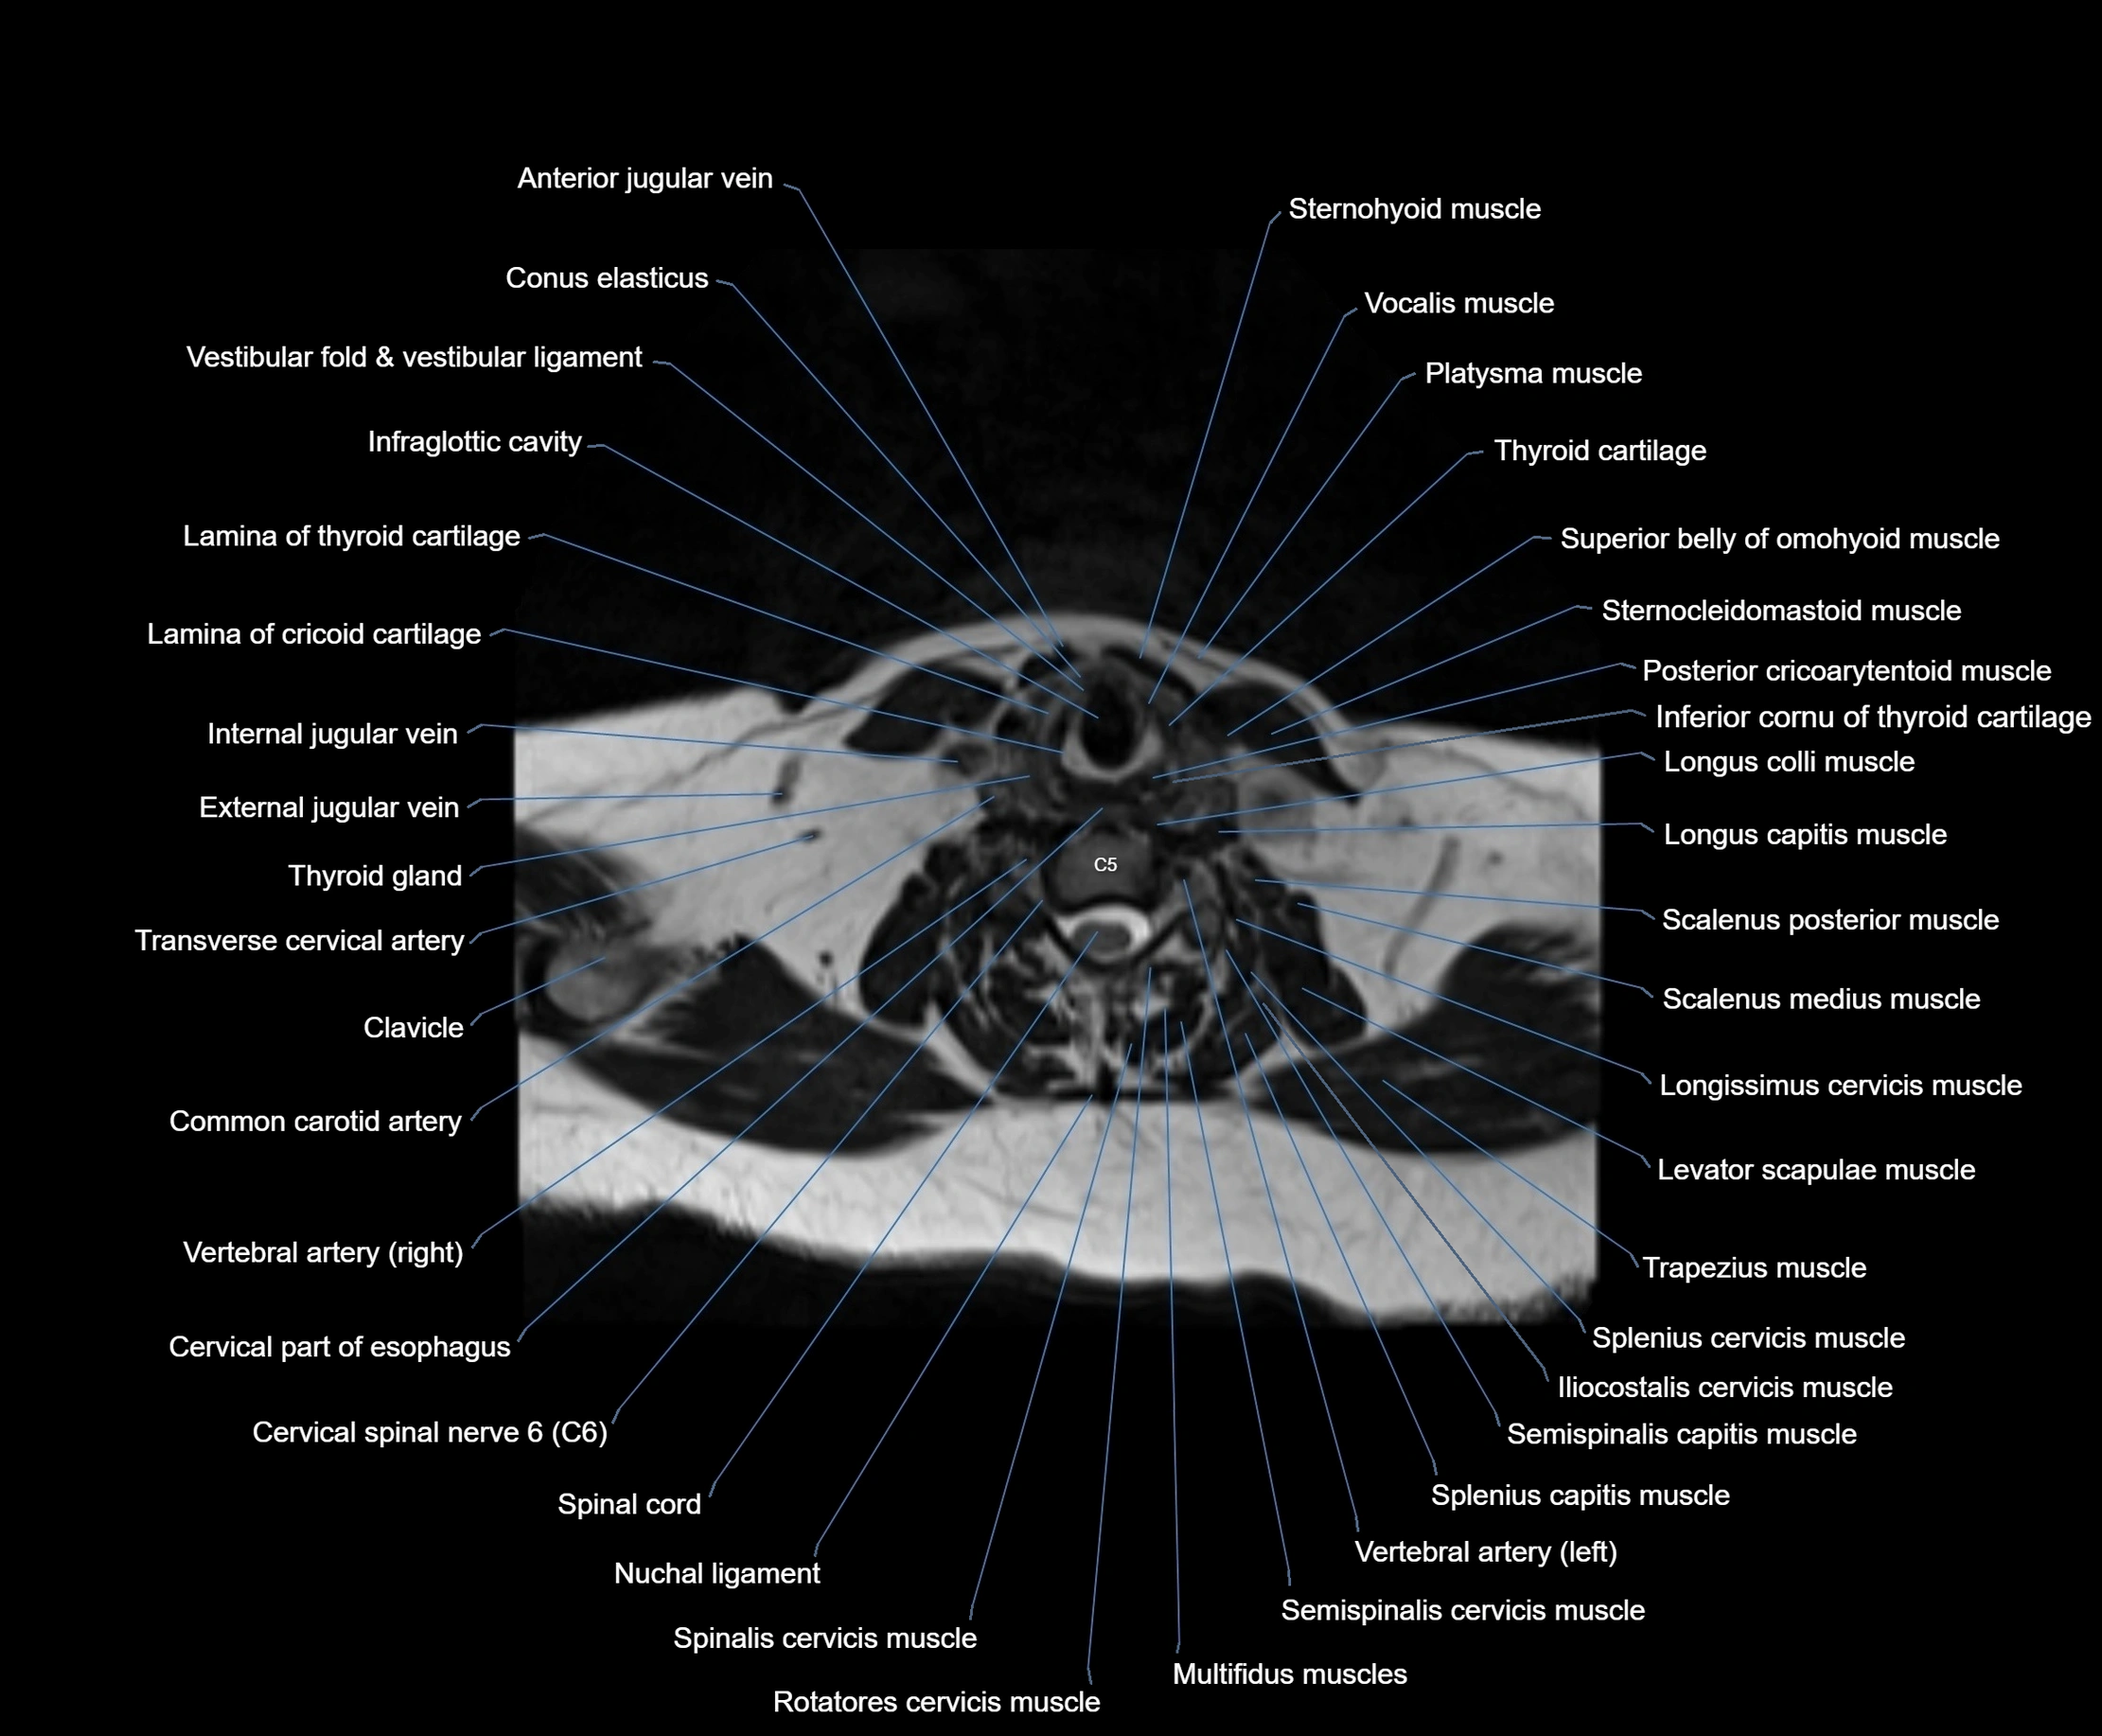

MRI images